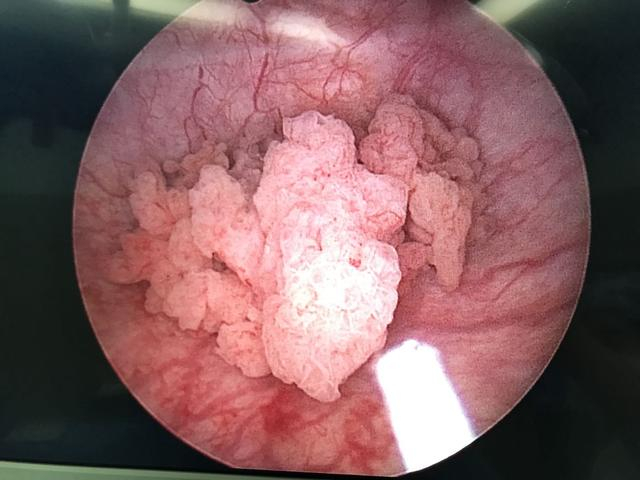

为进一步明确诊断,老许又接受了诊断性经尿道膀胱肿瘤电切术,术中发现,左侧输尿管附近有菜花状肿瘤,表面伴坏死,之后的病理检查显示:老许患上了浸润性高级别尿路上皮癌,肿瘤组织已经侵犯到了肌层。

典型膀胱肿瘤表现:菜花样新生物